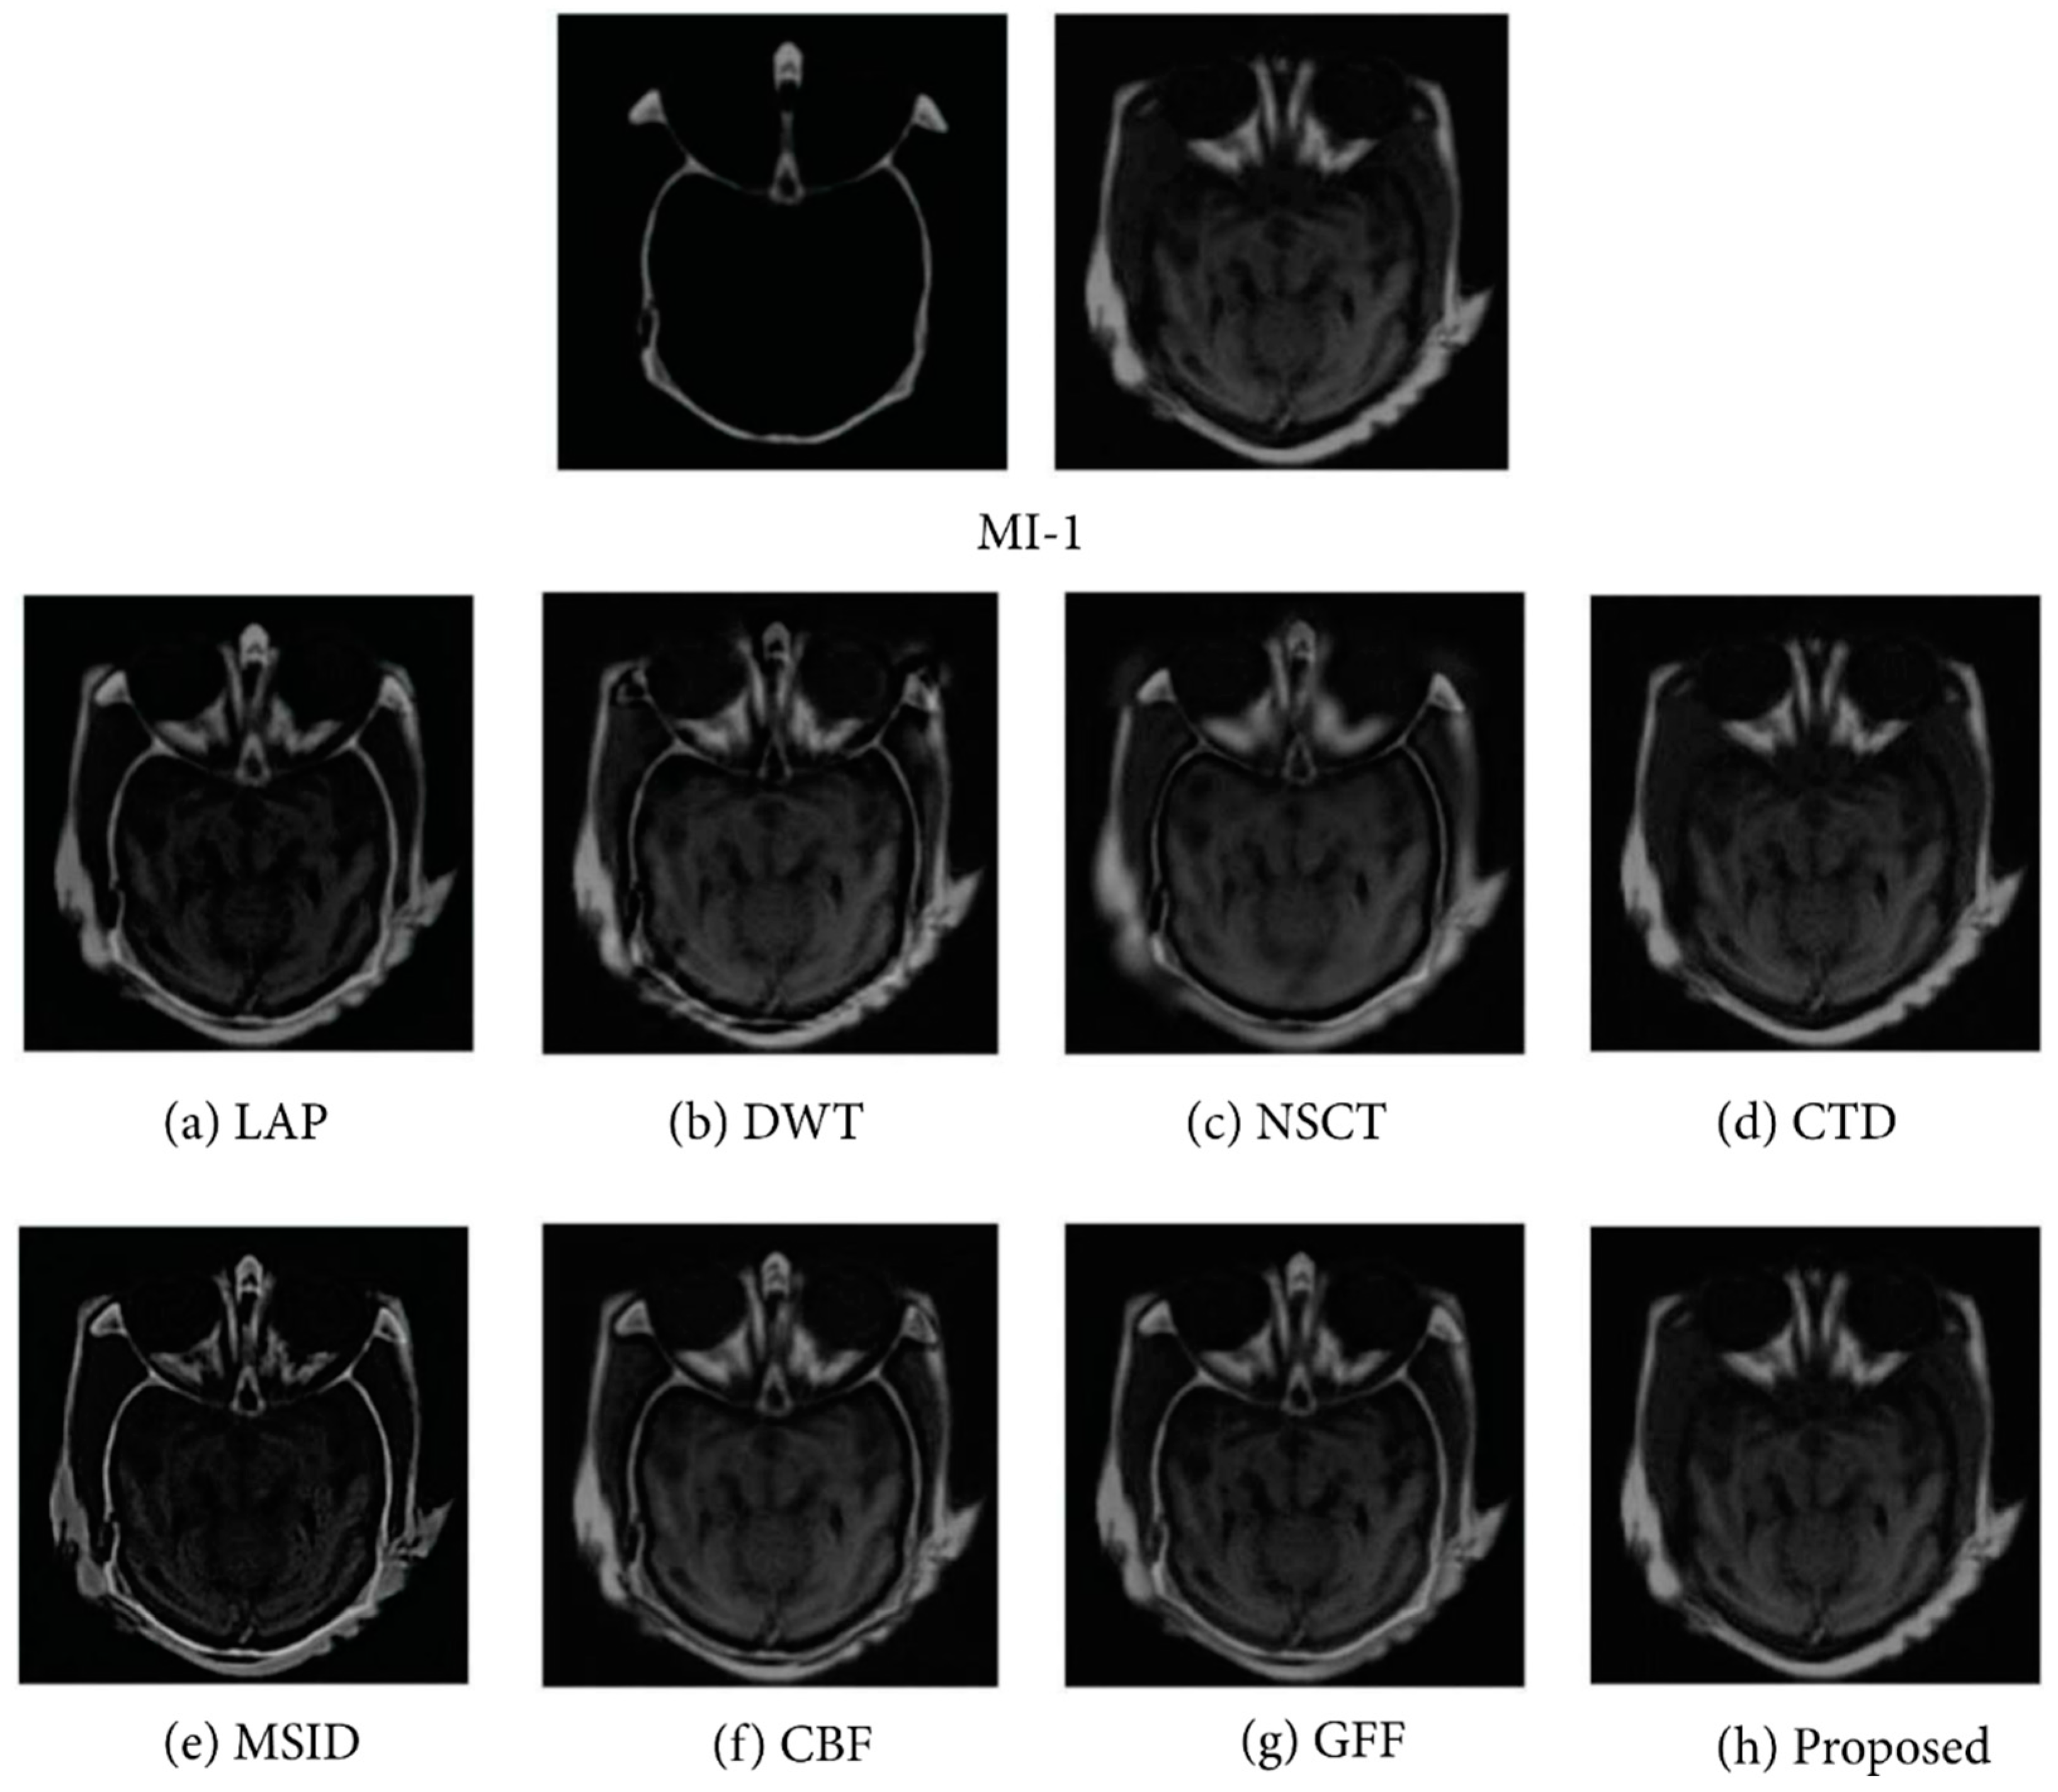

In data fusion, the combination of images and edges are also seen in a similar way as the image data fusion in Figure 4A. To combine the edge characteristics of sub-images, Wang et al. [52] presented a study to conduct pixel-level image fusion by using wavelet transformation algorithms to integrate multi-modal images and compared the fusion effect on MRI and PET images. The comparison experiments were conducted using three methods: high-pass filtering, weighted averaging, and traditional wavelet fusion. Moreover, according to the explanation of the feature-based data fusion approach which was proposed by Zhang et al. [53], they decomposed images from the source into two layers, detail layers and base layers, employing a local binary pattern method to obtain features in low-levels. Using saliency detection, the detail and base layers of the low-level features were used to construct weight maps. The map was adjusted by the fusion of both layers for continuing spatial stability among their corresponding layers and the images from the source. Then, the final output fused image was created by recombining mentioned layers appending the Laplacian pyramid, the discrete wavelet transforms, and the non-subsampled contourlet algorithms. In the investigation, they used nine pairs of medical images, e.g., MI-1, MI-2, MI-9 in testing image sets. The result of the testing image set MI-1 applying different algorithms with their proposed method is demonstrated in Figure 8.

Figure 8.

Outcome of the experiment “MI-1” was acquired using different fusion methods along with the proposed technique, e.g., decomposition, construction of decision map, sub-fusion of different layers, and image reconstruction. There are numerous traditional fusion methods based on mutual information levels and their associated enlarged regions. Reprinted with permission from reference [53], 2017, Zhang et al.